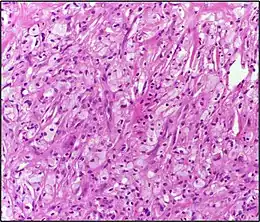

Histologie (Microscopie)

- Infiltrat dermique d'histiocytes géants parfois polynucléés (cellules de Touton) dont le cytoplasme spumeux est chargé de lipides : cholestérol essentiellement